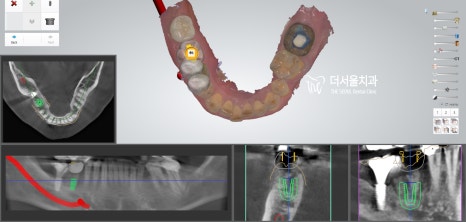

우선 정밀 검진을 통해

나타난 구강 문제를 확인해 보니

우측 어금니 거의 모든 곳에

염증이 나타나 있었습니다.

문제는 이런 곳이 한두 곳이 아니라는 것과..

병소가 생각보다 깊고 넓게 퍼져 있다는 것이죠.

표시해둔 곳을 보면 염증이 퍼져

치조골 소실까지 나타나 있는 곳도 있었습니다.

디지털 방식의 분석을 이용하여

식립 방향 및 각도를 결정하고

최종적으로 심어질 위치까지 선정했습니다.